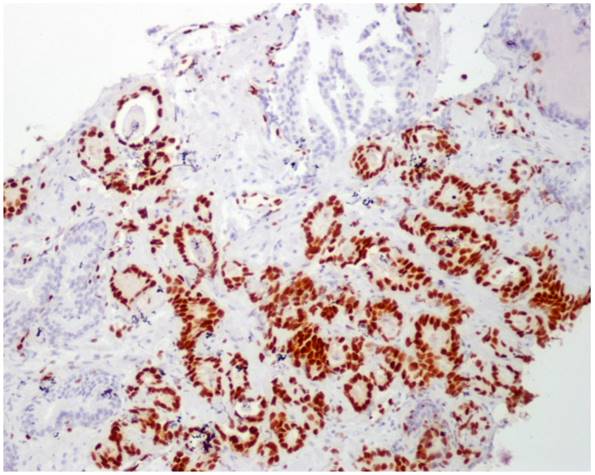

Both antibodies, ERG and AR, showed nuclear immunoreaction and it was subsequently graded using a semiquantitative scoring system as 0 (negative), 1 (weak), 2 (moderate) and 3 (strong) according to the intensity and percentage of stained glands (Figure 1). Appropriate internal and external controls were used. The histopathologic evaluation was performed by one experienced pathologist (MJM).

Figure 1

IHC staining strength for ERG (EPR3864) and AR

No immunoreaction to ERG was observed in PIN, benign samples, and in benign glands adjacent to adenocarcinoma in those tumor samples (Figure 2).

Figure 2

ERG immunoperoxidase staining showing the strong nuclear staining in the tumoral glands, while the benign glands have no nuclear immunoreaction to ERG (10X).